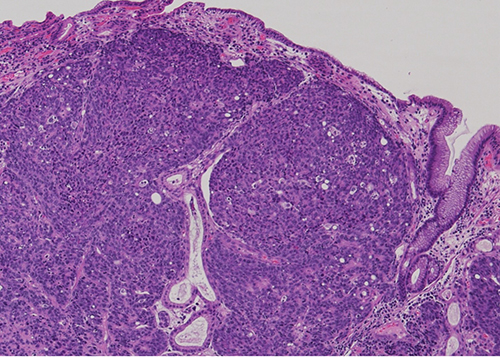

Figure 1 - Low power view: Gastric mucosa infiltrated by sheets of poorly differentiated malignant cells.

In this case, the histology showed sheets of poorly differentiated neoplastic cells with admixed predominantly neutrophilic inflammation. The neoplastic cells were positive for cytokeratins AE1/AE3 and CAM 5.2 consistent with carcinoma. They were diffusely positive for EBV by in-situ hybridization. DPC4/SMAD4, which shows loss of expression in approximately half of pancreatic ductal adenocarcinomas, showed retained expression. Immunohistochemical stains for mismatch repair proteins (MLH1, PMS2, MSH2, and MSH6) showed retained nuclear protein expression in the neoplastic cells. Immunohistochemistry for Her-2 was negative (score 0) and PD-L1 showed a combined positive score (CPS) of 5.

EBV was first identified in association with lymphoepithelial carcinoma of the stomach by Burke et. al. in 1990 (4). EBV-associated gastric carcinomas are often poorly-differentiated, consisting of irregular sheets, trabeculae, ill-defined tubules, or syncytia, and show prominent associated lymphocytic inflammation which may be intra- and/or peritumoral. In the 2019 World Health Organization (WHO) classification of digestive tumors, tumors with this morphology are categorized within the morphologic subtype of gastric carcinoma with lymphoid stroma (6). However, the morphologic spectrum EBV-associated carcinoma is variable and they may also show conventional tubular/intestinal adenocarcinoma morphology (5,7). Interestingly, our case showed intratumoral inflammatory cells, but they were predominantly neutrophils rather than lymphocytes. Positivity for EBV is typically established by in-situ hybridization by detection of positive signals within tumor cells.